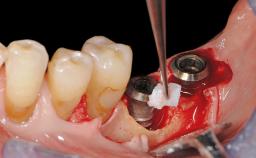

Resective Surgical Treatment of Peri-Implantitis Including Implantoplasty

In this case, Myroslav Solonko, Ignacio Sanz Sánchez and Mariano Sanz present a treatment that aims to eliminate exposed implant threads by modifying the implant surface, converting a moderately-rough surface into a smooth surface.